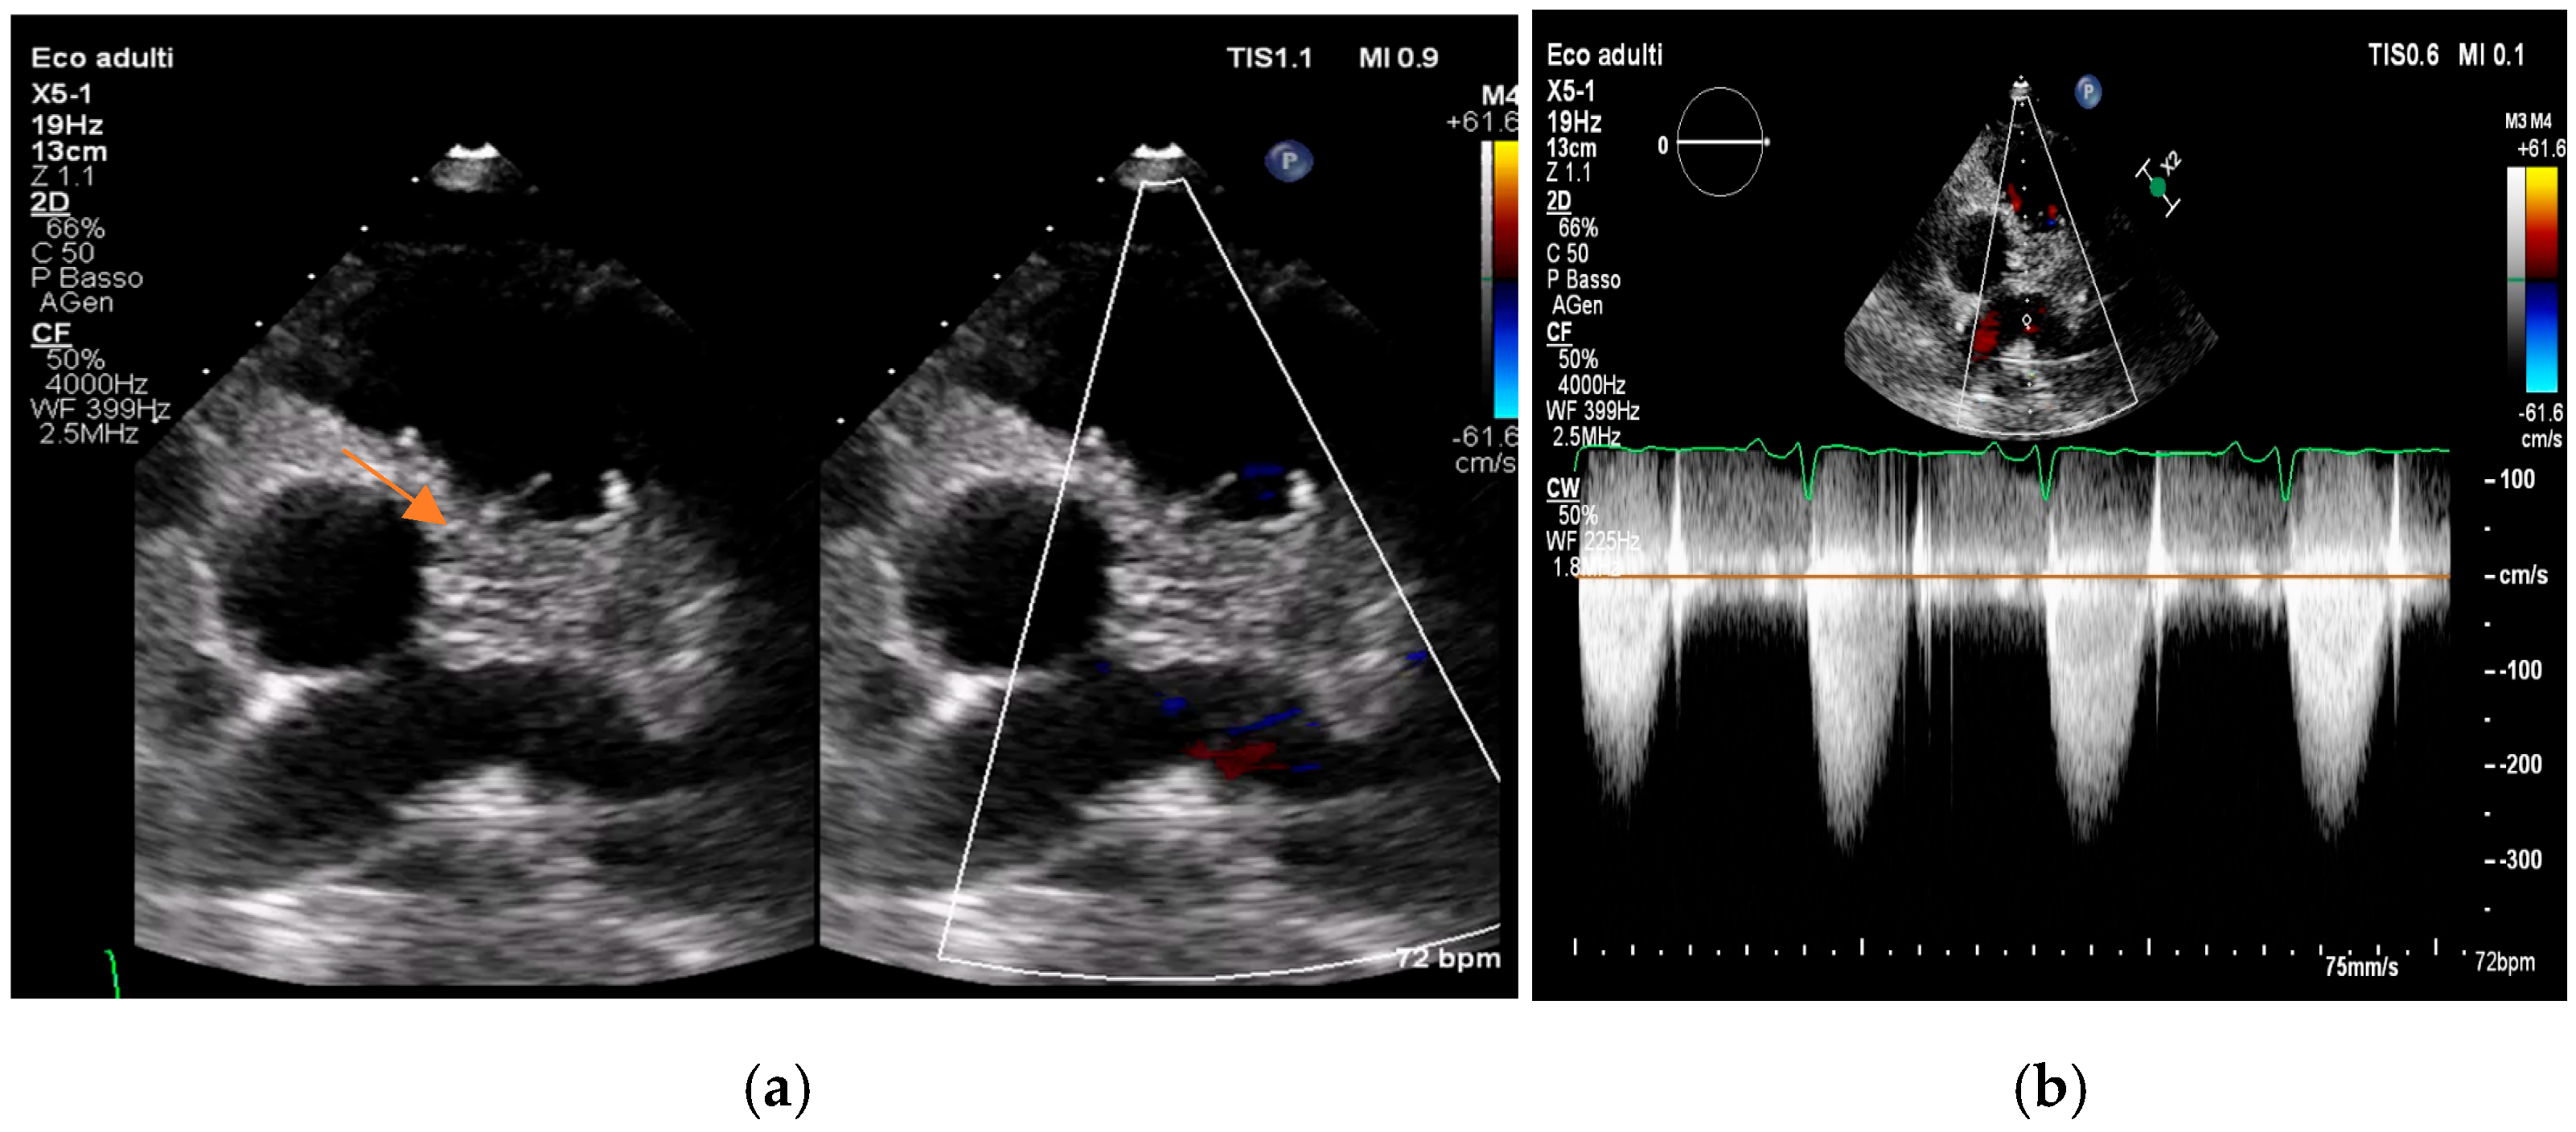

- valvular or leaflet perforation, i.e., tissue defects causing valvular regurgitation originating from the site of perforation.

- valvular aneurysm, a saccular outpouching of a valve leaflet, protruding into the atrium or ventricle.

- perivalvular or perigraft abscess, an echolucent or echodense area adjacent to the valve annulus or prosthetic ring often with irregular borders and sometimes with evidence of cavity formation.

- pseudoaneurysm, a contrast-filled outpouching with a narrow neck communicating with the cardiac lumen, often adjacent to the valve annulus. On echocardiography, it appears as a pulsatile cavity with systolic expansion and diastolic collapse.

- intracardiac fistula, visualized as an abnormal communication between cardiac chambers or vessels, is often detected by using color Doppler.

- significant new valvular regurgitation compared with previous imaging, i.e., increase in regurgitant jet size, vena contracta width…